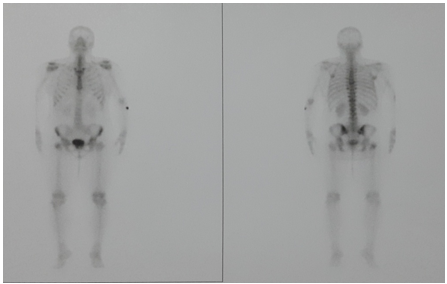

Tc 99m MDP bone scintigraphy revealed increased uptake at T7 vertebral body (Figure 3).

Figure 3: Bone scan revealed increased uptake at spinal thoracic level.

Radioisotope bone scan shows increased vascularity then decreased uptake at the site of diminished osseous tissue [1]. Tc scan & SPECT CT of our patient also revealed increased vascularity.